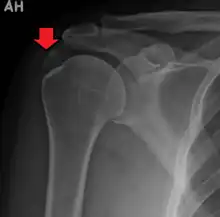

A plain X ray of the shoulder showing calcific tendinitis

Calcific tendinitis is a common condition where deposits of calcium phosphate form in a tendon, sometimes causing pain at the affected site. Deposits can occur in several places in the body, but are by far most common in the rotator cuff of the shoulder. Around 80% of those with deposits experience symptoms, typically chronic pain during certain shoulder movements, or sharp acute pain that worsens at night. Calcific tendinitis is typically diagnosed by physical exam and X-ray imaging. The disease often resolves completely on its own, but is typically treated with non-steroidal anti-inflammatory drugs to relieve pain, rest and physical therapy to promote healing, and in some cases various procedures to breakdown and/or remove the calcium deposits.